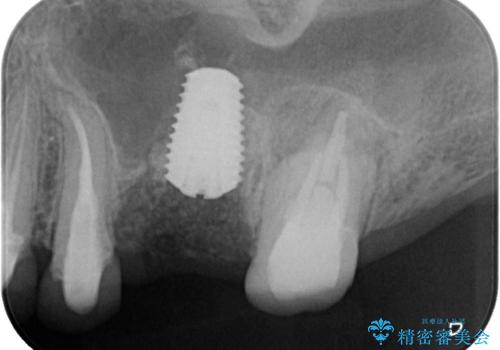

垂直方向への炎症が大きく、抜歯即時埋入はできたものの、即時荷重(インプラント埋入時の仮歯の装着)を可能とする安定値は得られませんでした。

それにもかかわらず、僅か4ヶ月で治療を終えることができ、以前の上顎洞底の挙上を行っていた頃よりも半年以上短縮することができました。